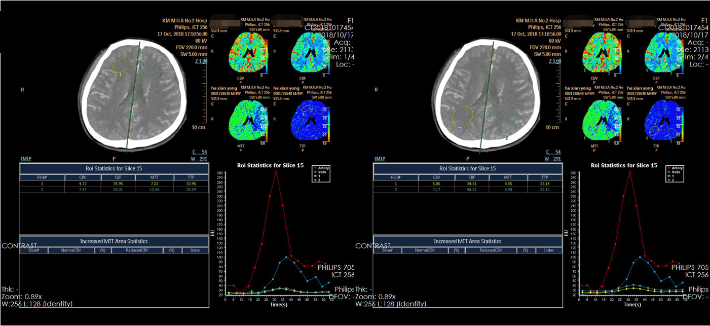

此次入院后,即予行全脑血管造影术,示左侧颈内动脉虹吸段重度狭窄。予患者家属充分沟通后,进一步行左侧颈内动脉虹吸段狭窄球囊扩张+支架植入术。

考虑狭窄段为夹层样改变,多角度导引导管造影,以更清晰地区分真假腔,选择最佳工作角度

微导丝通过狭窄血管段

放置微导丝远端至左侧大脑中动脉上干M2段

3mm*15mm球囊扩张

球囊扩张后

4.5mm*22mm Enterprise 支架

术 后

--DSA显示左侧颈内虹吸段狭窄约72%。前交通开放,右侧大脑前动脉通过前交通动脉向左侧大脑前动脉、大脑中动脉供血区有代偿供血。

✔支架选择:左侧颈内动脉虹吸段狭窄段长度较长,远端至左侧大脑中动脉M1起始段,近端至眼动脉开口上方。且此段血管迂曲,狭窄段近端、远端都有较大的血管转折,使用球扩支架风险很高。因此我们选用了顺应性较好,又有一定支撑力的自膨支架——Enterprise 支架。

✔术中要点:左侧颈内动脉虹吸段狭窄考虑为夹层,予反复多个角度导引导管造影,以明确真假血管腔,微导丝通过狭窄段血管时谨慎、轻柔操作,务必判断导丝应从真腔通过。先予球囊扩张,观察扩张后狭窄段血管管径恢复情况。释放前准确定位支架近端,远端,应完全覆盖狭窄血管段。